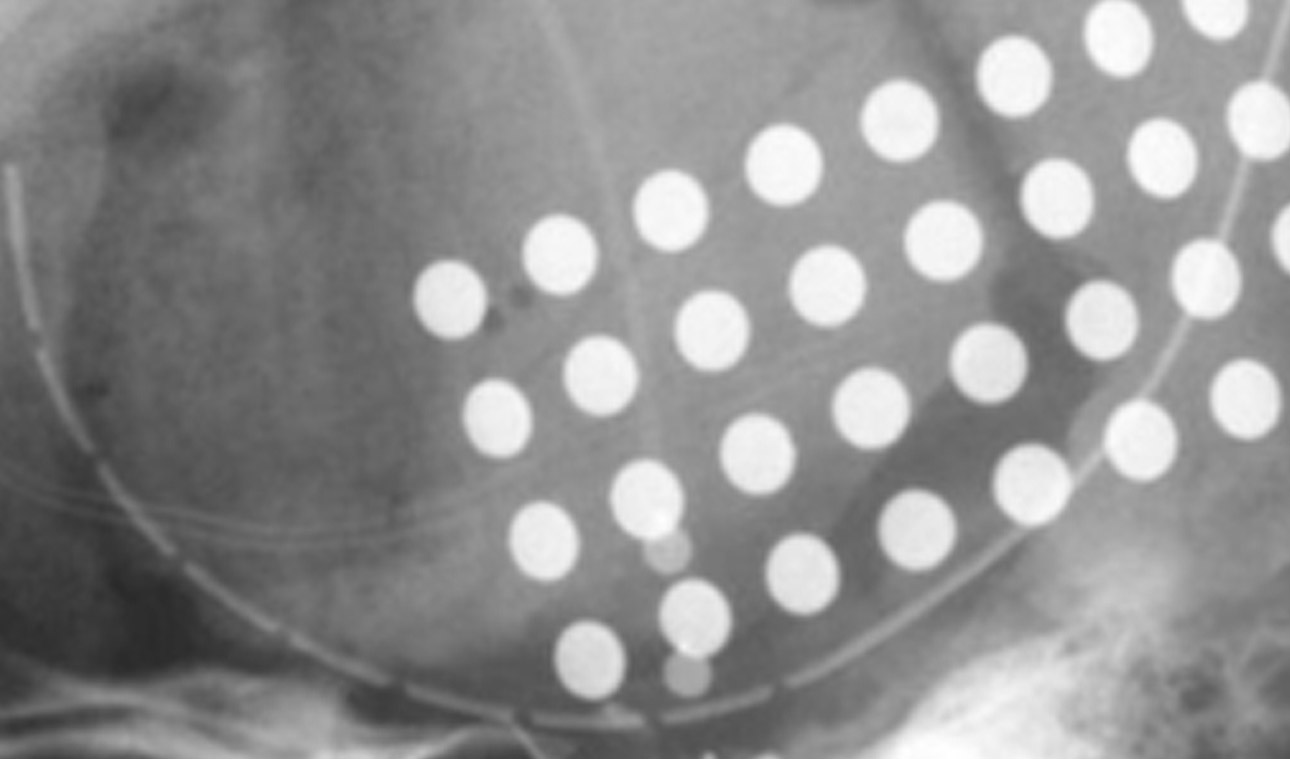

Vaskuläre Neurochirurgie

Die Klinik für Neurochirurgie ist Teil des Angiom-Zentrums Marburg zur Behandlung von Gefäßmißbildungen im Kopf- und Halsbereich, wobei in der Neurochirurgie im wesentlichen die intrakraniellen und spinalen Gefäßmißbildungen behandelt werden, und in der HNO-Klinik die extrakraniellen Gefäßmißbildungen....